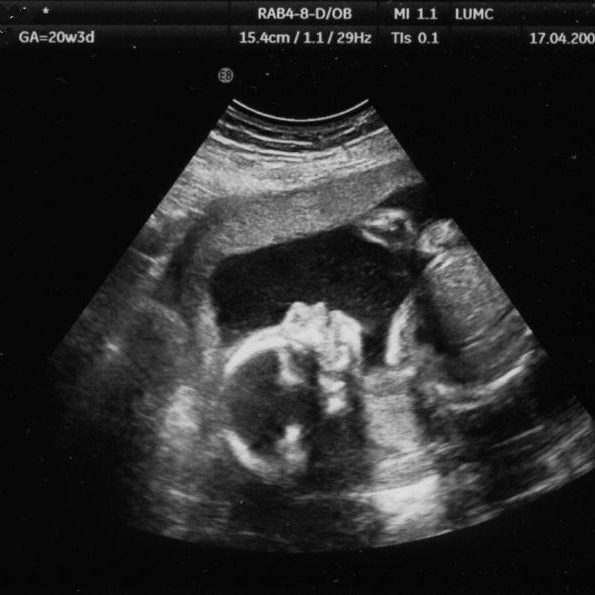

За гестациска трофобластна болест може да се посомнева доколку кај трудницата се појави ненадејно вагинално крвавење или доколку по абортус или породување, лохиите перзистираат абнормално долго време. Дијагнозата се поставува врз основа наултразвучен преглед и одредување на серумско β hCG. Моларна бременост (Mola Hydatidosa) е болест на плацентата која се карактеризира со трофобластна хиперплазија и…